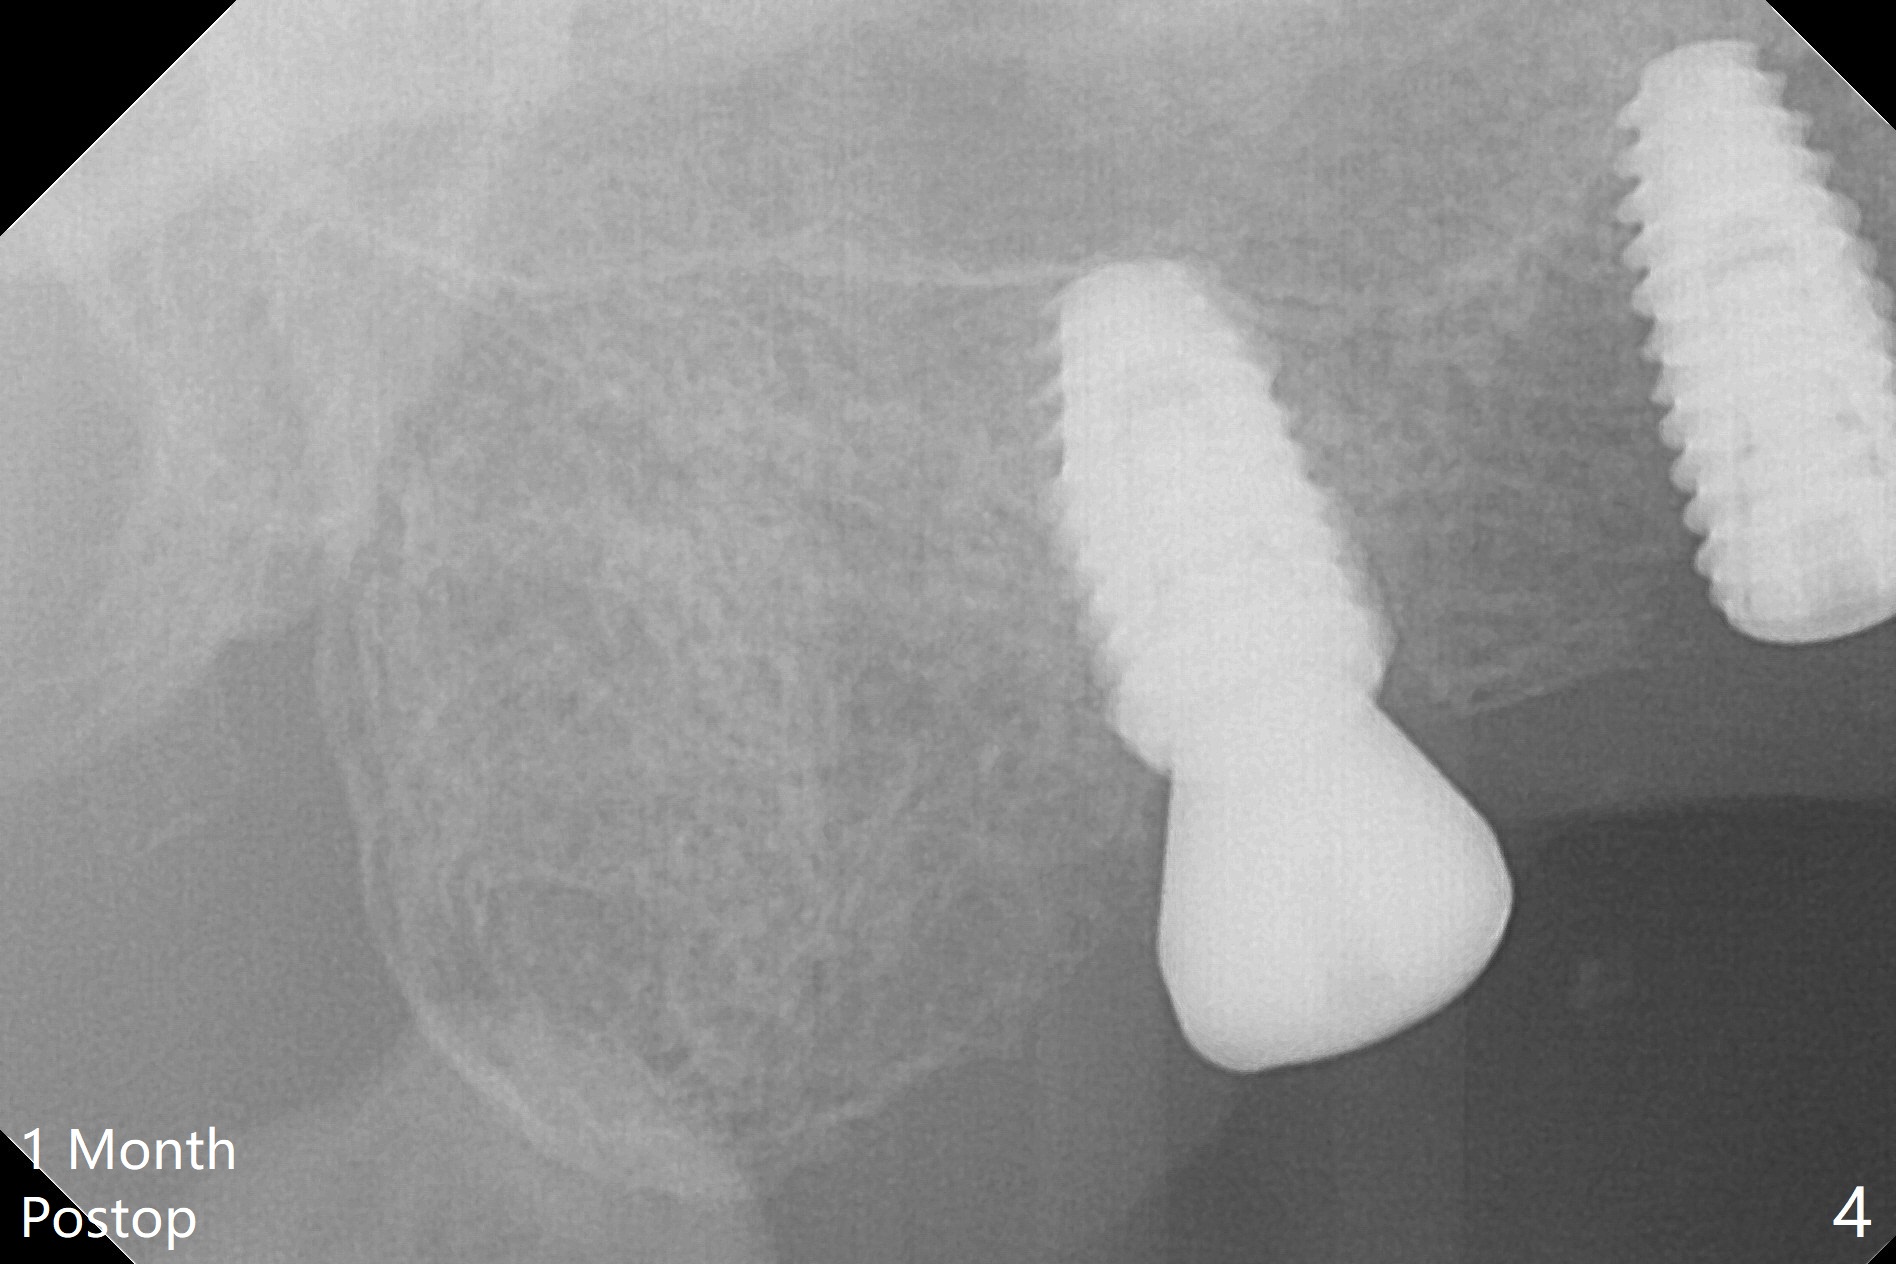

Osteotomy at the sites of #2 and 3 goes on as planned. Sinus lift using DIO 2.8 mm round bur with 6 and 7 mm stoppers (respectively) is carried on without certainty, because it is difficult to feel the stop through the osteotomy. The crest may be uneven or soft. It appears that the soft tissue landmark as a stop may be easier to identify. In fact a 3 mm IBS Magic Expander (an osteotome) was used for sinus lift at #3. The 2 implants are placed with 20 and 30 Ncm (Fig.1,2). Healing abutments are inserted. At 2-week follow-up, the patient reports "pain a few days earlier, took a pill of antibiotic, pain gone. UR metal is sharp". She does not take antibiotic regularly. Exam reveals that there is heavy plaque around #2,3 healing abutments. The buccal edge of #2 abutment is trimmed for comfort. Nearly 1 month postop, #3 healing abutment dislodges with buccal gingival erythema and edema with purulent discharge (Fig.3). Healing screw is placed at #3 with Amoxicillin and Chlorhexidine prescribed. One week later, the implant at #3 turns when the healing screw is retightened (Fig.4). After debridement, Vanilla graft is placed. There is no infection at #2 or 3 four months postop (Fig.5,6); the lingual gingiva is erythematous and edematous at #29 with mobility II (Fig.7 (vertical root fracture)). Uncover is conducted at the site of #3; there is no infection superficial 7.5 months postop (Fig.8). There is a large buccal defect upon incision with dark hemorrhage. In fact the bone density is low crestally (Fig.8 *). Bone graft is placed for the 2nd time. Eleven months later (1.5 years post implant placement), the bone regrows crestal (Fig.9 *). The crown at #3 is loose 1 year 5 months post cementation (Fig.10). After proximal trimming (Fig.11 *), the abutment at #3 is seated completely. After lab repair, crown oral cement, crown/abutment removal for excess cement removal, the crown/abutment cannot be torqued >25 Ncm (Fig.12, 30 Ncm). PA shows incomplete seating (Fig.12 <). Then the crown is sectioned so that the abutment has more freedom to be seated completely with pressure against the gingiva (the patient feels pain, Fig.13). Torque is 30 Ncm. After crown cementation, the abutment will not be removed for cement removal.